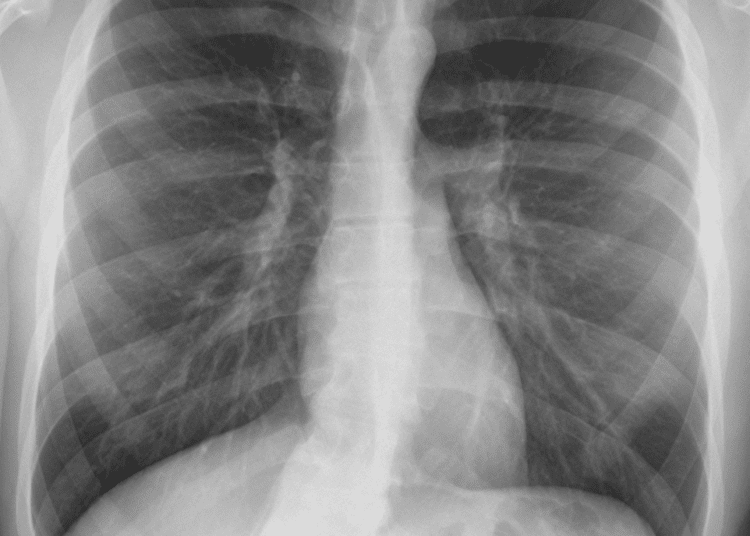

Dr. Tushau Prasad, Emergency Physician, Wockhardt Hospitals, Mira Road, said, “In our initial assessment we came to know that his airway was clear since he could speak full sentences but he didn’t have any breath sounds on the right side of his chest. His X-Ray revealed that there was an air-trapping happening under the skin on the right side. We realized that it was a traumatic chest injury wherein the stabbing object had penetrated through the chest wall hurting blood vessels and with its tip injuring the pleura, contributing developing of pneumothorax (air enters the pleural space). Such traumatic cases, if not handled immediately lead to loss of life because of a condition called pneumothorax wherein the lung collapses as the air leaks into the space between the lung and chest wall. This air pushes on the outside of the lung and makes it collapse and compresses the heart due to the expanding pressure.”

Dr. Prasad added, “The patient was put on oxygen support first and then a needle decompression of the chest cavity was done. It is the process by which the air in the lungs is released. Stab or penetration wounds on the chest have high mortality rates. In patients with suspected Pneumothorax, Needle Thoracostomy is a life-saving procedure and should be done as soon as possible followed by a chest tube which was inserted in the chest to release air trapping due to pneumothorax and help him to breathe properly. The patient was also put on blood transfusion because the blood pressure was critically low that is 67/42 mmHg and the patient had lost significant blood. Slowly, his BP came to normal range, his breathing improved. Later, his CT scan showed a remarkable improvement. After a short stay of 4 days, the patient was discharged with complete recovery.”